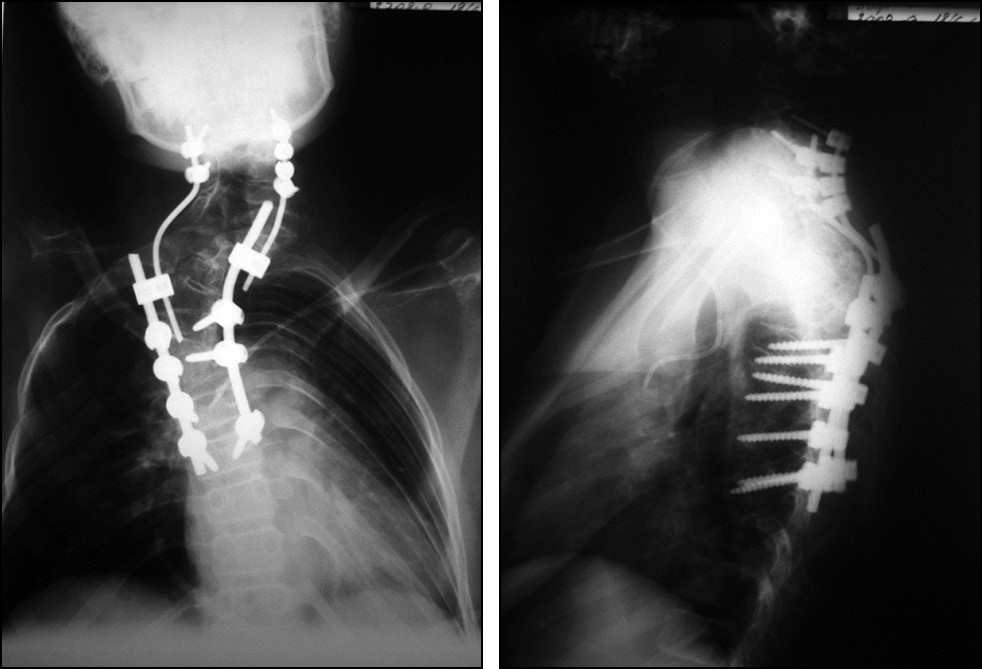

В связи со сложностью деформации и прогрессирующим нарастанием неврологической симптоматики принято решение о проведении многоэтапного хирургического лечения. На первом этапе пациенту установлено Halo-кольцо с последующим выполнением дозированной Halo-pelvic тракции. Во время проведения Halo-pelvic тракции отмечен частичный регресс неврологического дефицита в виде снижения спастичности мышц (с Ashworth 3 до Ashworth 2), а также появления сгибания пальцев стоп. С целью фиксации деформации и декомпрессии спинного мозга выполнен второй этап хирургического лечения в следующем объёме: ламинэктомия на уровне С7–Тh2, транспедикулярная фиксация на уровне С2–Th8 и задний спондилодез костными аутотрансплантатами (рис. 2). Послеоперационный период протекал без особенностей, рана зажила первичным натяжением, швы сняты на двенадцатые сутки. В течение нескольких дней после второго этапа отмечена положительная динамика неврологического статуса в виде отчётливого увеличения мышечной силы в нижних конечностях. Через 3 недели пациент уже был способен самостоятельно встать с кровати с дополнительной помощью ухаживающего, а также с опорой на ходунки передвигаться в пределах палаты. Через 4 недели неврологический статус соответствовал группе D по шкале Frankel.

Рис. 2. Постуральные рентгенограммы после второго этапа операции. Стержни грудного и шейного отдела соединены двухосным коннектором типа «домино».

Fig. 2. Postural radiographs after the second stage of the operation. The thoracic and cervical rods are connected by a biaxial “domino” connector.